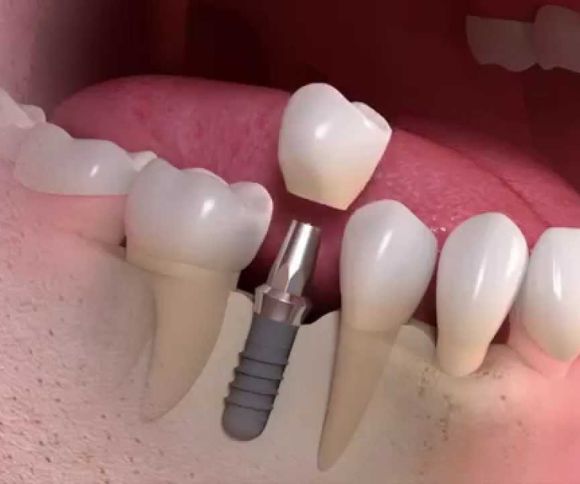

• ডেন্টাল ইমপ্লান্ট: যদি দাঁত এতটাই ক্ষতিগ্রস্ত হয় যে এটি সংরক্ষণ করা সম্ভব না, তাহলে ডেন্টাল ইমপ্লান্ট স্থাপন করা হয়। এটি একটি স্থায়ী ও কার্যকর সমাধান।

1. হারানো দাঁতের স্থানে প্রাকৃতিক দাঁতের মতো ইমপ্ল্যান্ট স্থাপন।

2. টাইটানিয়াম ইমপ্ল্যান্ট ব্যবহার করে দাঁতের স্থায়ী সমাধান।